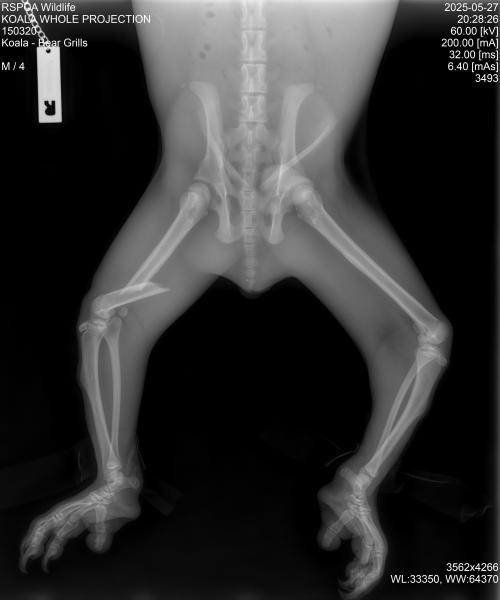

THE INCREDIBLE tale of survival of the Logan koala affectionately named ‘Bear Grills’ is being used by Logan City Council in Queensland to urge drivers to slow down during koala breeding season.

The young male koala was hit by a car on Mundoolun Road in Mundoolun and became lodged in the car’s grill as the vehicle travelled to the base of Tamborine Mountain.

“I’m pleased to report that Bear Grills is healthy and recovering well after undergoing surgery for a fractured thigh,” Ms Colbran said.